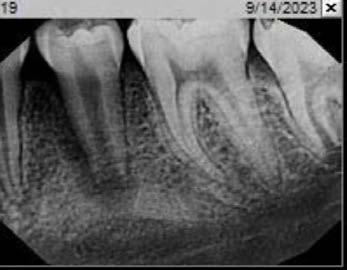

Technique for extracting tooth or root tip from underneath fixed partial denture emphasizes use of magnification from dental loupes or dental surgical operating microscope for precision when performing technique-sensitive procedure. Case report.